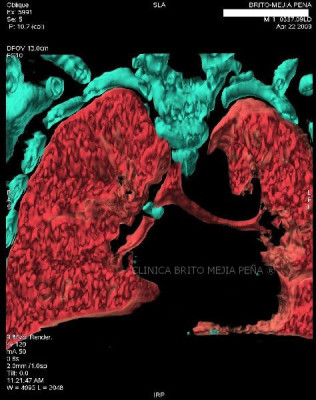

Fibrosis y enfisema pulmonar